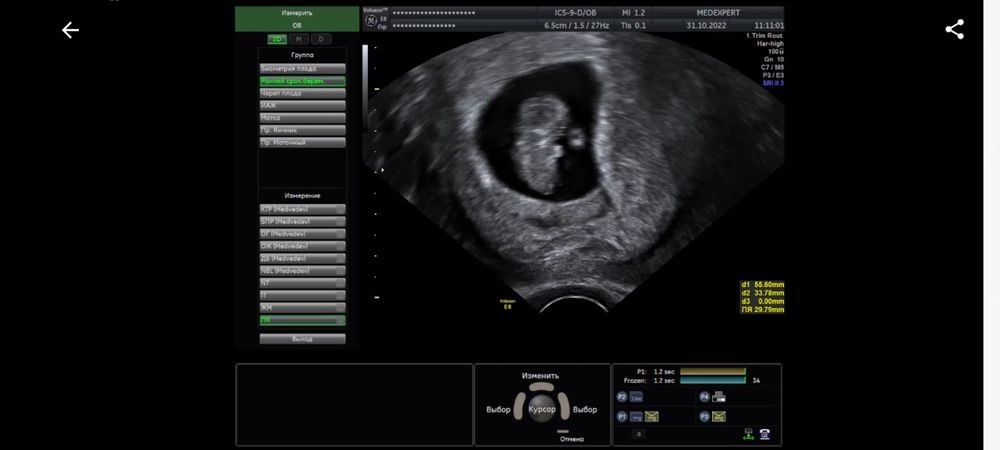

Ретрохальная гематома и мягкая шейка 9 недель беременности

9 недель и 3 дня срок. Сегодня сделала узи, по причине того, что в прошлый раз была отслойка 11×3мм (заключение прикладываю). В результате сегодня имеем прогрессирующую отслойку 27×3мм. Помимо этого шейка матки очень мягкая и губы свободно двигаются при перемещении датчика. Иногда тянет живот, не сильно, как перед месячными, только намного слабее. Выделения по цвету немного желтоватые, но не постоянно, а раз за несколько дней. А так, нормальные по цвету, без запаха. Кровяных или коричневых выделений нет. Прием у акушера-гинеколога только завтра. Приговор врача-узи заставляет нервничать и переживать, но пытаюсь отвлечься и успокоиться, была озвучена угроза прерывания беременности. Приехала домой и соблюдаю постельный режим до завтрашнего дня. Встаю только по крайней необходимости (туалет, покушать). Из препаратов ничего не принимаю, только витамины Элевит первый триместр. Как мне вообще вести себя в данной ситуации до приема врача? Чего бояться и при каких ситуациях вызывать скорую. Короче я напугана.